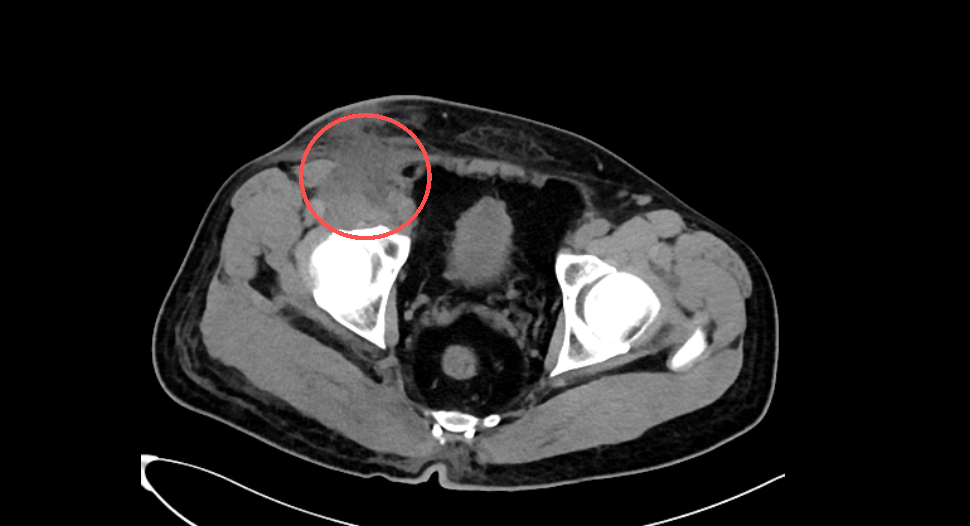

術前ct照